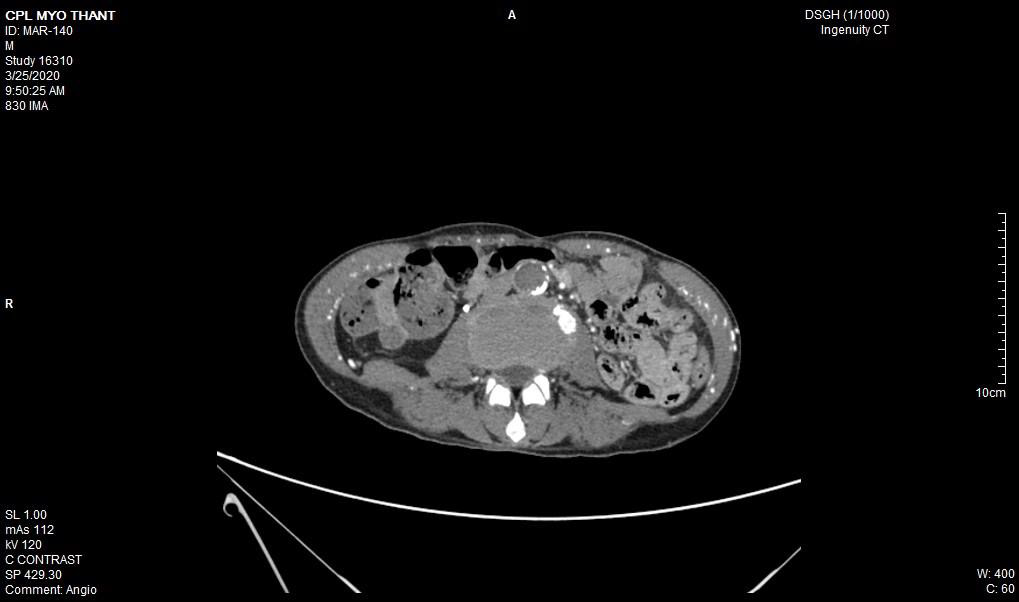

As his left femoral artery pulsation became weak and thus, CT Aortogram was done (4 weeks after symptom onset of right femoral artery occlusion). It revealed extensive thrombosis with complete obstruction of abdominal aorta starting below the level of celiac trunk- both renal arteries and both iliac arteries. The calcifications of the arterial wall at aortic arch, thoracic and abdominal aorta and both iliac vessels were seen too. (Figures 5-11) Thus, he had severe atherosclerosis due to hypertension and heavy smoking. Occlusion of both renal arteries explained his high blood pressure. The cholesterol and uric acid level were normal. He was treated with atorvastatin, aspirin, clopidogrel, antihypertensives, wound care, physiotherapy, intensive nursing care nutritional support and antibiotics.

This patient had on going ischaemia as the wound was not healing well and diminished left femoral pulsation. And it was a clinical clue to arterial obstruction at higher level – above femoral artery. It was proved by CT angiogram.

Regarding the aetiology of arterial occlusion in this 43-year-old patient, relatively young age, severe atherosclerosis was the main culprit as there were extensive atheromatous plaque in wall of the whole aorta and it was aggravated by smoking and hypertension. It was the main reason for reporting this case. Moreover, It was not due to COVID-19 infection because it was excluded initially though there were few case reports having deep vein thrombosis, pulmonary embolism and arterial thrombosis due to COVID-19 infection [11-13].

In essential thrombocythemia, recurrent thrombosis of same artery was seen in some cases [7,8]. Moreover, thrombosis at multiple site was reported too [14,2]. It commonly causes obstruction of small vessels and rarely to median and large arteries. Nevertheless, there were reports on essential thrombocythemia producing thrombosis of aorta [15-17]. In this case, combination of hypertension, smoking, severe atherosclerosis and essential thrombocythemia gave rise to extensive thrombosis of aorta; the rare variety of this case.